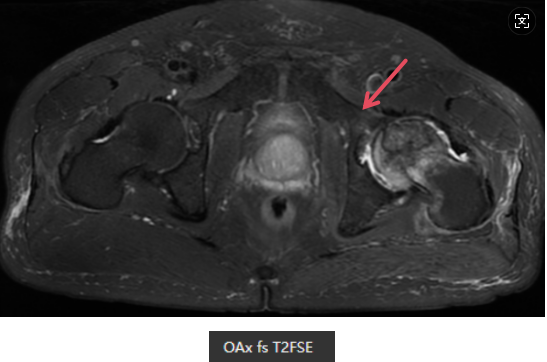

MR表现

左侧股骨头变扁,局部塌陷,骨质内见线状T1WI低信号,髋臼及股骨近端骨松质见片状T1WI低、T2WI压脂高信号,DWI高信号,周围滑膜增厚,邻近软组织肿胀,PD压脂信号增高,关节腔少量积液。